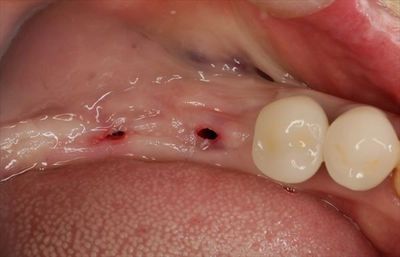

減張切開して縫合封鎖しました。

1週間から10日後に抜糸します。

オペ終了時のレントゲン写真です。

埋入トルクは充分でしたので6週後には仮歯で咬んでいただける予定です。